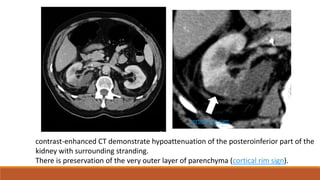

contrast-enhanced CT demonstrate hypoattenuation of the posteroinferior part of the

kidney with surrounding stranding.

There is preservation of the very outer layer of parenchyma (cortical rim sign).

cortical rim sign